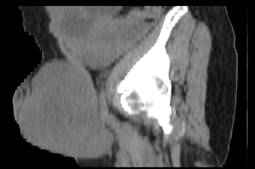

Figura 1: Tomografía computarizada simple de pelvis, cortes a 3 mm con reconstrucción MPR sagital